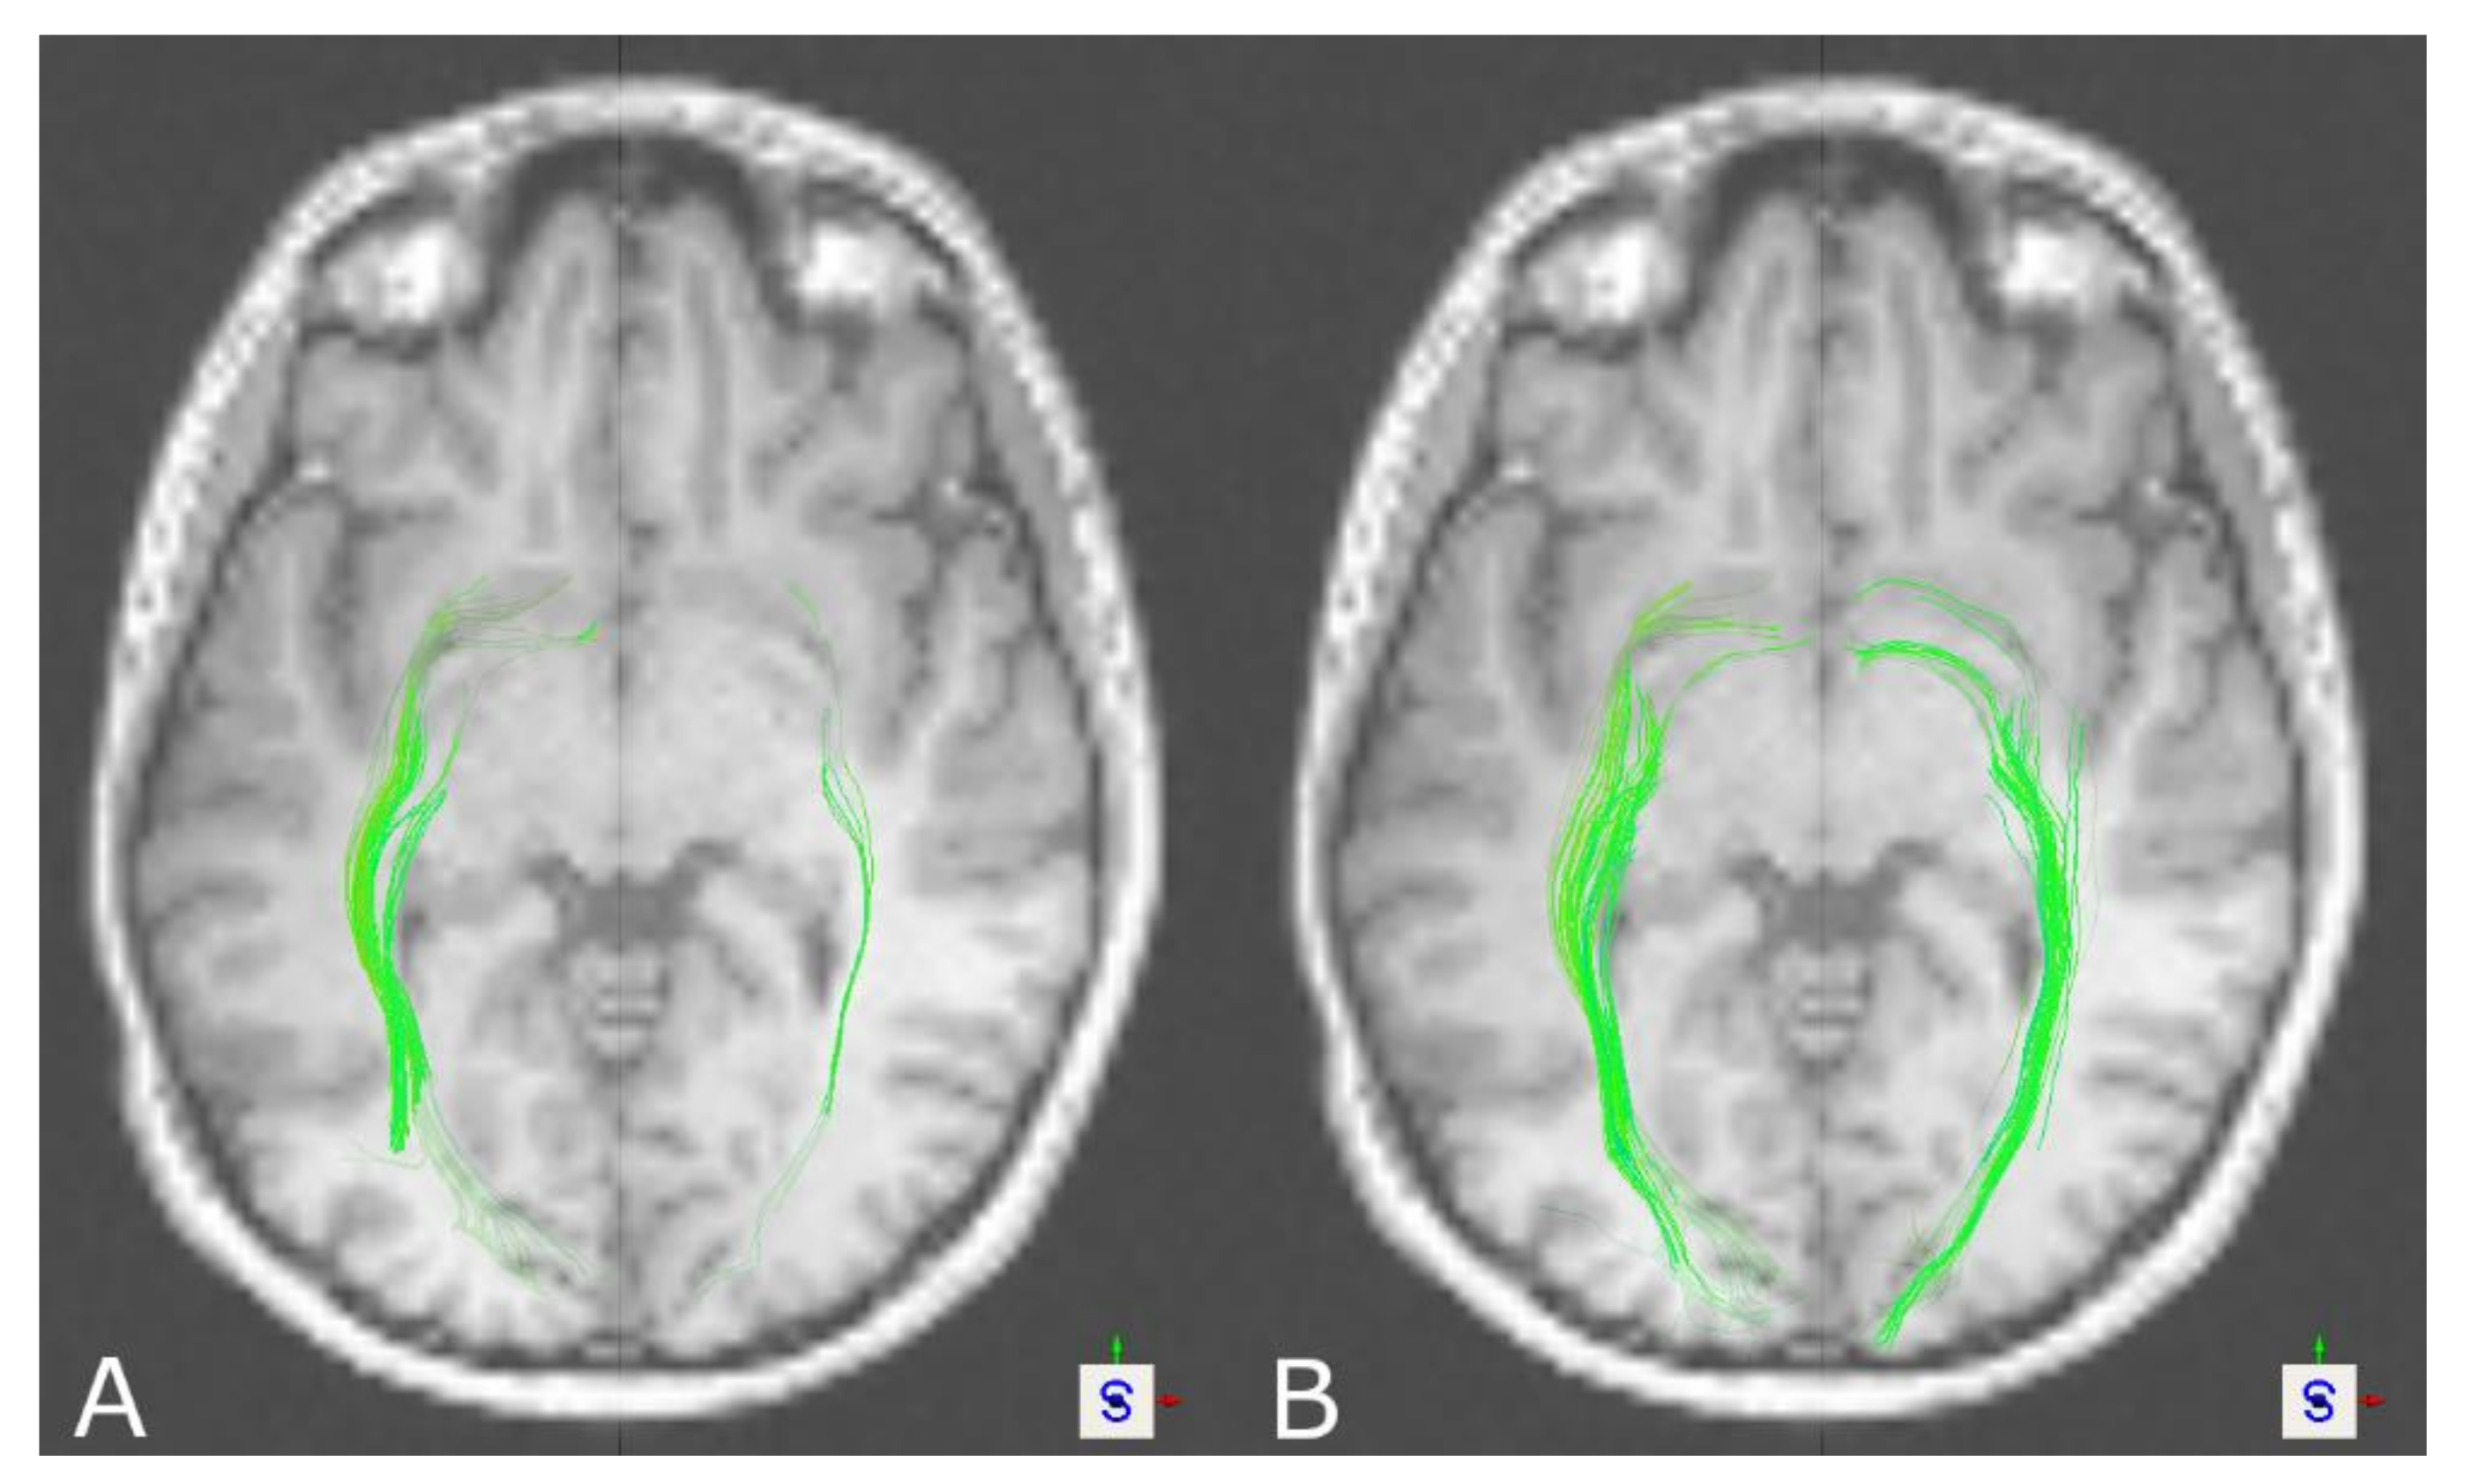

3.2. The Optic Radiation